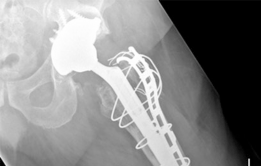

Reconstruction techniques : Acetabulum— augment buttress, morcellized bone grafting, porous tantalum shell. Femur—modular revision stem, trochanteric plate, cerclage cables (Figs. 19.20 and 19.21).

7. #### Postoperative Radiographs

(Figs. 19.20 and 19.21)

4. Femur—since the patient had a long-stem cemented femoral component, we elected to perform an extended trochanteric osteotomy to gain access to the cement mantle and to aid in the extraction of the femoral component. We also elected to use a trochanteric plate with several cerclage cables and an allograft strut to augment stability for the revision femoral component. A modular femoral revision component that gave primary diaphyseal fixation was chosen due to severe proximal femoral bone loss secondary to osteolysis.